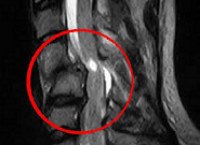

На диагностическом этапе пациент с миелопатией, имеющий в анамнезе травму позвоночника, должен быть осмотрен не только неврологом, но и травматологом. Неврологический осмотр и проведение электрофизиологических исследований (ЭМГ, ЭНГ) помогают установить уровень спинального поражения. Определить состояние костных структур на этом уровне позволяет проведение рентгенографии позвоночника, а лучше - КТ позвоночника. Наиболее исчерпывающую информацию о состоянии спинного мозга на сегодняшний день дает МРТ позвоночника. Она позволяет определить характер спинального поражения, степень компрессии спинного мозга, выявить наличие грыжи диска, эпи- или субдуральной гематомы, гематомиелии. Данные МРТ используются для решения вопроса о целесообразности хирургического лечения. При невозможности использования КТ или МРТ прибегают к контрастной миелографии. Однако этот диагностический метод менее информативен и опасен развитием осложнений.